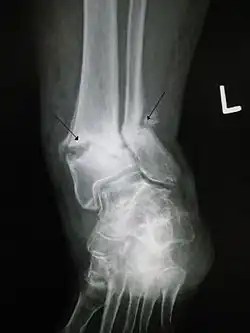

Nieprawidłowy zrost złamanej kości

Kryteria czasowe nie mogą być ściśle określone. Umownie staw rzekomy jest rozpoznawany, jeśli po upływie 9 miesięcy od urazu (złamania kości) nie ma zrostu kostnego, a na zdjęciach rentgenowskich nie ma postępu gojenia złamania przez kolejne 3 miesiące.

Objawy stawu rzekomego można podzielić na kliniczne i radiologiczne. Kliniczne to utrzymywanie się dolegliwości bólowych w miejscu złamania, szczególnie w obciążeniu kończyny, ruchomość patologiczna, nieco wyższa temperatura kończyny w miejscu złamania. Do objawów radiologicznych należy widoczna szczelina przełomu w czasie, kiedy powinien być już widoczny zrost kostny.